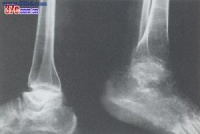

本病是在骨发育过程中发生的全身性、多发灶性、软骨坏死性疾病,造成的骨关节损害将持续终身,X

线征象归纳如下:

1.干骺端边缘模糊或凹凸不平,呈波浪状以至锯齿状。如病变继续发展,指骨端不整齐的边缘可呈碎裂现象。此时,关节无明显变形。

2.以骨骺与骨干开始融合为特征。骨骺自中央部分开始融合,渐扩展到边缘,骨骺本身亦有破坏、分节、不整等现象,也可能完全被吸收。干骺端可呈杯口状凹陷,骨髓嵌入其中而早期愈合,停止发育。

3.干骺完全融合,骨的纵向发育停止,病骨变短变粗。因为各干骺的融合迟早不同,以致各指骨可呈现长短不齐,骨端宽大变形,使关节粗大。

4.如干骺端愈合以后的青年发病,临床症状多见且严重。关节相对骨端都有损害,可影响整个关节,表现为大骨节畸形,可伴有短骨干。

由于病人发病年龄、受累部位、病变发展阶段不同,X线有不同表现。原苏联与国学者曾主要依据于部X线改变将本病分为以下几型。

⑴、干骼型:以干骼端改变为主,包括临时钙化带变薄、模糊、中断、消失,干骼端出现凹陷、硬化等。干骺型发生于学龄前及学龄儿童,反映骺板软骨坏死后的继发变化,代表大骨节病较早的损害,临床症状多为阴性或非常轻微。干骺型的X线变化除很明显的硬化在非病区儿童中较少见外,其他征象均可在非病区儿童中出现。因而在同一地区没有发现Ⅰ度以上典型病例的情况下,不宜仅凭某几点干骺端X线改变就诊断为本病。前面谈过的日本发现的所谓大骨节病,就是由于没有充分注意到这一点。⑵、干骺骨骺型:除上述干骼端变化外,骨骺也有变化,如骨骺常呈锥状或其他变形,嵌入凹陷的干骺端等。此型多发生于学龄及青春期,反映骺板软骨的一部分发生全层坏死,其干骺侧和骺核侧同时有生长障碍和骨质变化,局部骺板早期穿通化骨。这是干骺型的进一步发展。

⑶、骨端型:以骨端改变为主,包括骨性关节面模糊不整、变薄、中断、凹陷变形、硬化、甚至碎裂等改变。多发生于学龄儿童至青春期以后年龄段,反映关节软骨深层坏死继发的骨质改变。骨端的变化发展较慢,合并其他关节损害多。骨端出现变化的诊断意义比干骺端的变化更重要,更具有特异性。

⑷、骨关节型:见于骺线闭合、骺板软骨消失之后,包括骨关节面的严重破坏、凹凸不平、增生硬化、骨刺形成、骨质碎裂、囊性变、骨端粗大畸形等改变。常累及多关节,X线所见类似退行性(增生性)关节病,是本病的晚期表现。